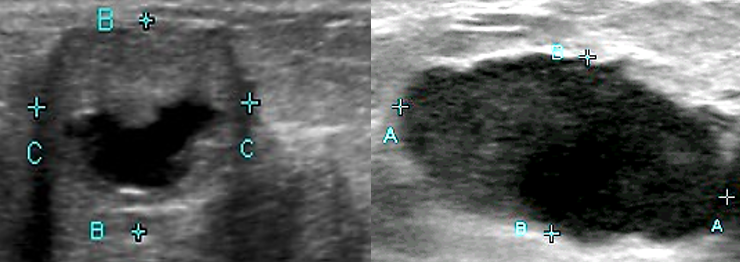

what is WES sign?

contracted GB with stone

Wall- linear anterior wall of GB

Echo- echogenic gallstone

Shadow- posterior to gall stone

what is shown?

WES sign

wall can be difficult to visualize